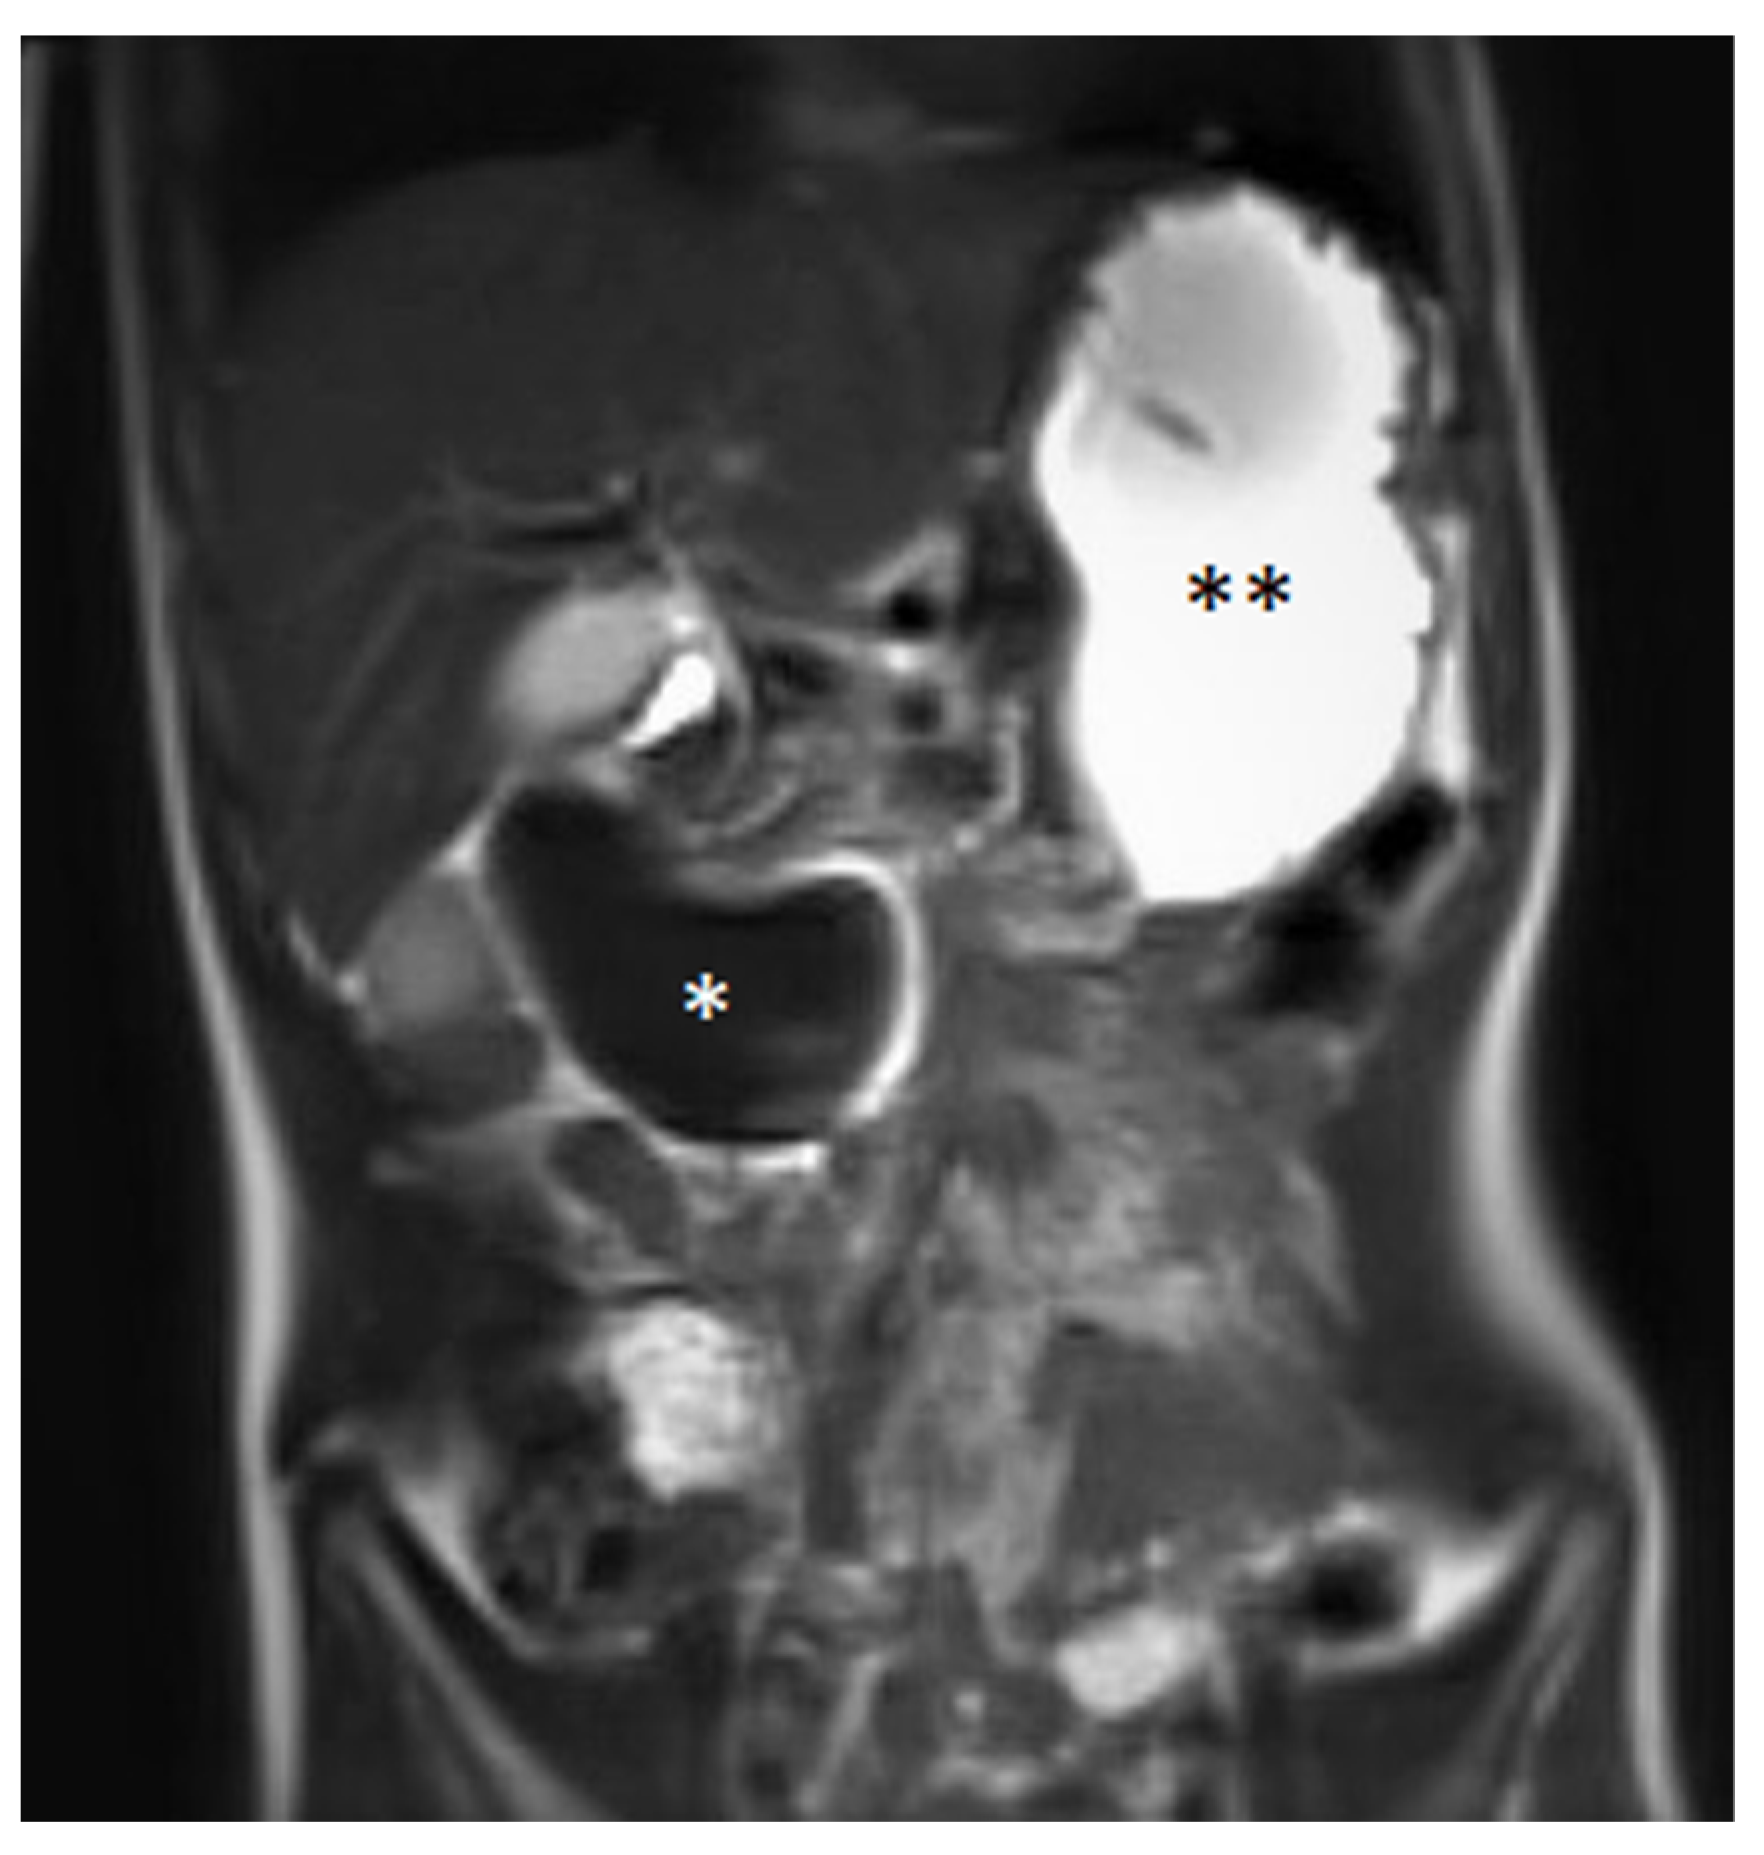

A blood examination, including hemoglobin value (9.2 mmol/L—normal value (nv): 7.4–9.1 mmol/L), platelet count (441 Gpt/L—nv: 150–530 Gpt/L), prothrombin time (94%—nv: 70–130%), partial thromboplastin time (24.1 s—nv: 27–40 s) and the international normalized ratio (1.03—nv: 0.8–1.25) gave no evidence of impaired blood clotting or anemia. Prior to the procedure, no further coagulation diagnostics were available due to the inconspicuous medical and family history of bleeding. The initial ultrasound (Figure 1) examination revealed the suspicion of a large IDH causing a mechanic ileus of the proximal small intestine. The subsequently performed magnetic resonance imaging (MRI, Figure 2) confirmed the suspected diagnosis—a large IDH in the area of the duodenal C with an extent of 62 × 36 × 35 mm that completely compressed the intestinal lumen in the sense of mechanical ileus.

Figure 2.

Coronal magnetic resonance imaging in the T2 HASTE sequence showing a large duodenal hematoma (*) and an ileus of the proximal small intestine with the filled stomach (**). Image quality is reduced due to the patient being restless.